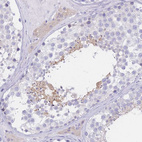

Immunohistochemical staining of human duodenum shows moderate cytoplasmic positivity in lymphoid cells.